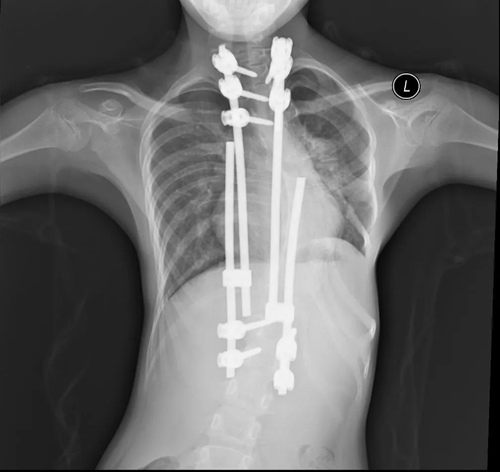

8歲女孩依依(化名)診斷為“先天性房間隔缺損”,合并有“嚴(yán)重的脊柱側(cè)彎”,曾先后于北京接受5次脊柱矯治手術(shù)并在椎骨植入鈦合金矯正支架。1年前依依曾于外院接受房間隔缺損介入封堵治療,遺憾的是手術(shù)未能成功。因此,入院后醫(yī)護(hù)人員為依依進(jìn)行了詳細(xì)檢查評(píng)估。依依的胸部CT檢查提示左側(cè)肋骨缺如伴胸廓畸形,外科開胸手術(shù)修補(bǔ)房缺創(chuàng)傷大,可能影響胸廓修復(fù)。心臟中心團(tuán)隊(duì)仔細(xì)評(píng)估房缺位置及形態(tài)后,符合介入封堵手術(shù)條件,依然決定實(shí)施房缺介入封堵治療。因依依脊椎植入鈦合金支架,常規(guī)透視下經(jīng)導(dǎo)管介入治療手術(shù)視野遮擋,心臟中心團(tuán)隊(duì)為孩子實(shí)施單純經(jīng)胸超聲引導(dǎo)下房間隔缺損封堵術(shù),手術(shù)順利完成。